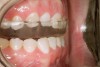

Figure 1  Classic presentation of the bruxism triad. Lateral wear pattern, generalized buccal tooth loss from erosion and abrasion, and history of sleep disruption.

Figure 1